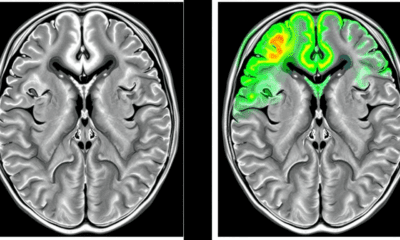

Our ability to store information about familiar objects depends on the connection between visual and language processing regions in the brain, according to a new study.